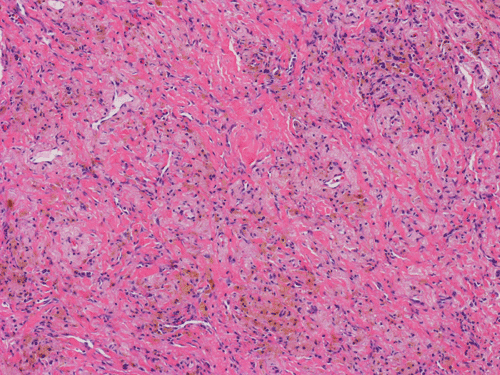

At scanning magnification (Panel A), the lung parenchyma is replaced by some coalescing fibrous nodules. The degree of involvement is variable at different fragments (Panel B and C). In the less affected areas, there are some fibrotic thickening of the septa (Panel C). In some areas, the changes are minimal and the pleural appear to be uninvolved (Panel D and E). In low to medium magnifications, these nodules of fibrosis contains a large number of hemosiderin laden macrophages (Panel F and G) admixed with fibrous tissue. The diagnostic tissue, however, is present in areas with increased cellularity. In these areas, there is a background of cells with a moderate amount of cytoplasm and bland nuclei. Some of these nuclei have kidney shape (arrow in Panel H). In some areas, many of the nuclei have a deep nuclear groove that resemble a coffee bean (arrow in Panel I). In the third type of areas, the nuclear grooving is not distinct (Panel J). Prominent eosinophilic infiltrations are almost always present. Immunohistochemistry on CD1a revealed many positive cells (Panel L). Also present in the specimen are multiple small blood vessels with thickened intima (Panel K). A Movat pentachrome stain demonstrates an internal elastic layer in these vessels and confirms that these are arteries (Panel M and N).

In this case it was utilized for two purposes. Since usual interstitial pulmonary fibrosis was one of the differential diagnosis, this stain can be used to demonstrate coexisting old and young/cellular fibrosis. Old fibrosis would appear yellow and the young fibrosis would appear blue-green (ground substance). It proved to be negative. The second purpose (not originally intended) was to help emphasize the thickened intimal layer seen with the associated vasculopathy.

In the end stage, the exhausted lesions are predominantly fibrotic and largely depleted of LCs. In some regions, the fibrosis may surround cystic spaces of variable diameter to form large areas of honeycombing. This is especially predominant in the upper lobes. In cases where parenchymal scaring is present, the pulmonary function will be largely compromised. At this stage, both pulmonary function tests and radiologic findings may suggest diffuse lung disease, but biopsy will show stellate fibrotic lesions centered on the terminal airways with no identifiable interstitial inflammation. Pulmonary vasculopathy (in areas of lung remote from parenchymal nodules) is also seen in late stage PLCH. Vasculopathy manifests as intimal fibrosis, medial hypertrophy or luminal obliteration involving both venules and arteries. This may account for pulmonary hypertension seen late in PLCH.